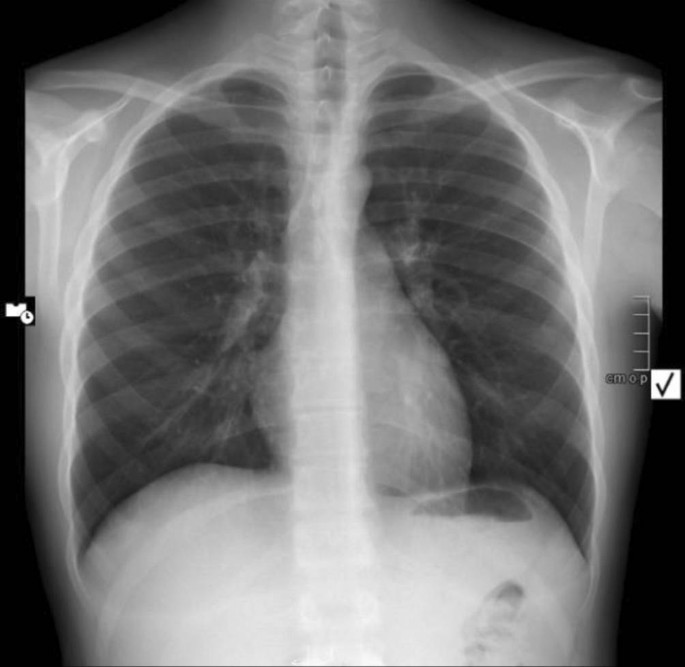

Nach der Aufnahme in die Notaufnahme wurde weiters ein Röntgen-Thorax in der p.-a.-Projektion im Liegen während der Akutdiagnostik durchgeführt (Abb. 1).

Abb. 1

figure 1

Bilaterale multiple, vorwiegend perihiläre, vaskuläre und interstitielle Konsolidierungen, deutlicher auf der linken Seite ausgeprägt (weiße Pfeile). Normaler Herzschatten

Dabei zeigten sich multiple perivaskuläre und interstitielle perihiläre, konfluierende Transparenzminderungen in Ober- und Mittellappenanteilen, ohne Zeichen der kardialen Dekompensation, am ehesten mit einem akuten Lungenödem vereinbar. Da die Echokardiographie eine pulmonale Hypertension moderaten Grades zeigte, entschied man sich für die Durchführung einer Thorax-Computertomographie zum Ausschluss einer Lungenembolie, und zwar mit der Einverständniserklärung der Eltern, auch wenn die akute Lungenembolie eine eher unwahrscheinliche Verdachtsdiagnose bei einem 15-Jährigen war (Abb. 2 und 3).